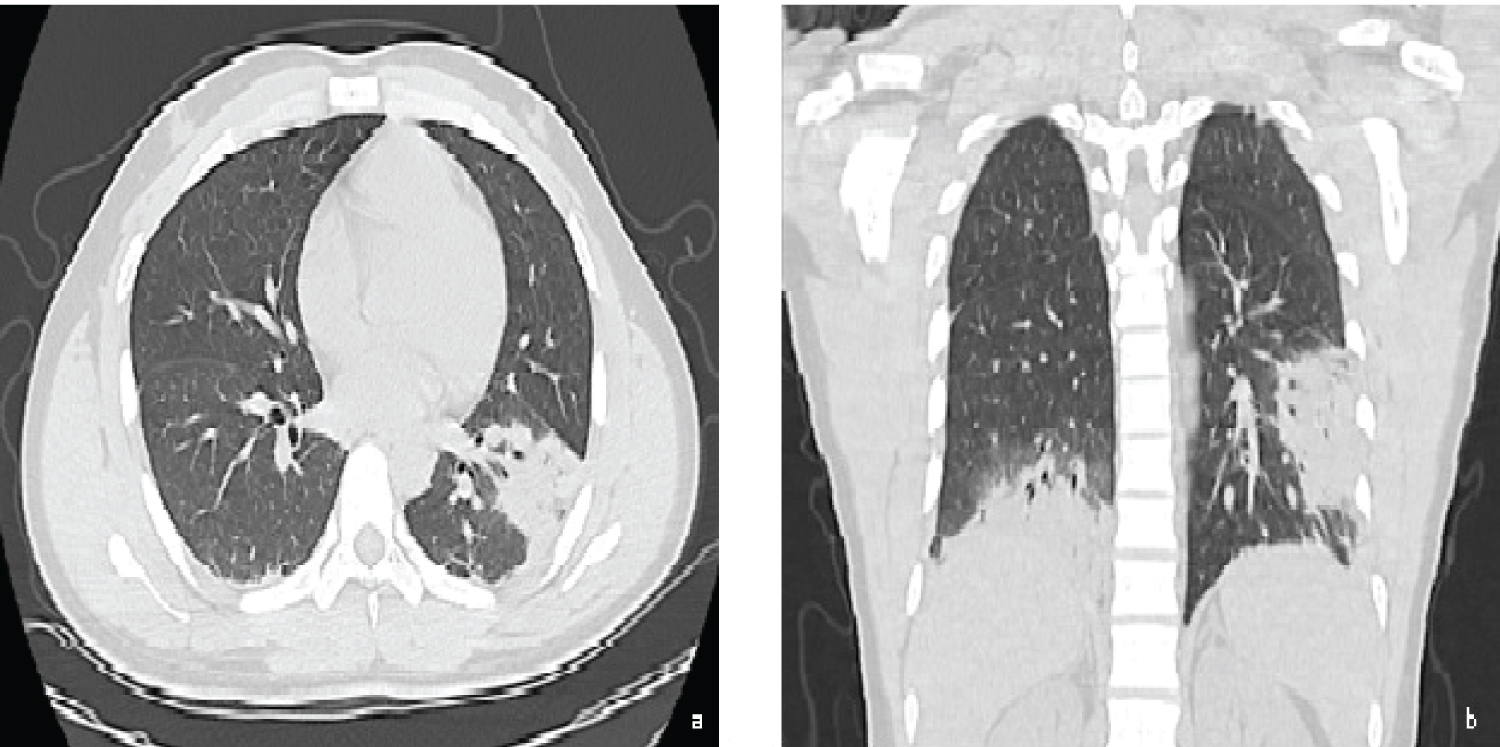

We report the case of a 24-year-old man who presented to our department with a 7 day history of fever, headache, chest pain and non-productive cough. There was no relevant clinical history or medication. On physical exam he had tachypnoea, inspiratory crackles in the left lung base and a peripheral oxygen saturation (SpO2) of 89%. Laboratory findings revealed normal white blood cell count, an increased high-sensitivity C-reactive protein (27.9 mg/dL N.R. < 0.5 mg/dL), lactate dehydrogenase (296 U/L > 250 U/L) and erythrocyte sedimentation rate (120 mm/h < 20 mm/h) with procalcitonin value within the reference range (0.09 ng/mL < 0.5 ng/mL). Chest radiography showed diffuse opacity of the lower third of the left lung. Chest CT displayed diffuse bilateral ground-glass opacities with baseline bilateral rounded consolidations (Figure 1).

Figure 1: Chest CT: a) Axial and b) Coronal; images demonstrating diffuse bilateral ground-glass opacities with baseline bilateral rounded consolidations. View Figure 1